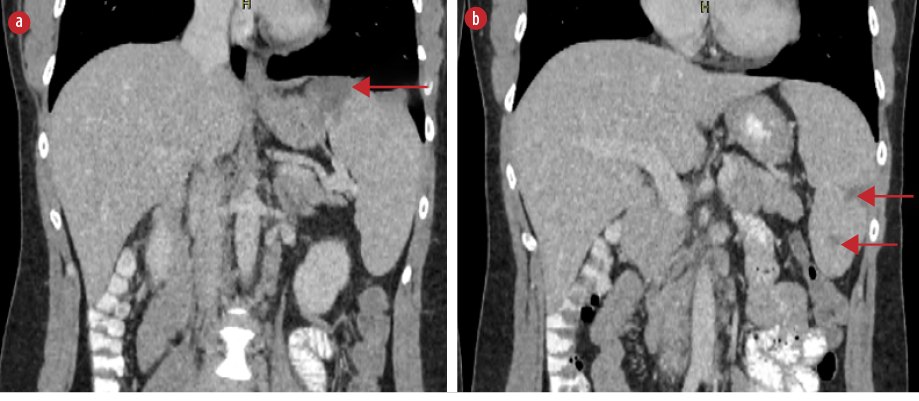

On the fifth day of hospitalization, the patient complained of new-onset left upper quadrant abdominal pain. Clinical examination revealed mild tenderness in the left upper quadrant and a palpable spleen. Computed tomography (CT) of the abdomen with intravenous contrast demonstrated multiple enlarged iliac lymph nodes, hepatomegaly (178 mm in the midclavicular line), and moderate splenomegaly (140 mm in the longitudinal axis). Multiple hypodense splenic lesions were visible without contrast enhancement, suggestive of splenic infarcts [Figures 1 and 2]. CT angiography of the abdomen showed no thrombi in the splenic vasculature. Hypercoagulability workup revealed mildly reduced protein S activity. Molecular testing for inherited thrombophilia (Factor V Leiden, Factor II-prothrombin, Factor XIII, MTHFR, and JAK2 V617 gene mutations) yielded negative results [Table 1]. Transesophageal echocardiography showed no evidence of thrombi, vegetation, or other abnormalities.

Figure 2: Coronal abdominal CT scan with intravenous contrast demonstrating multiple splenic infarcts (red arrows), (a) located at the superior, as well as (b) the middle and lower parts of the spleen.